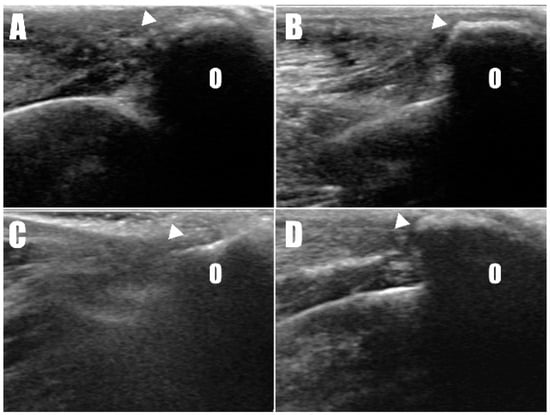

A 2-year-old, 4.5 kg, intact female Pomeranian was referred to a veterinary medicine teaching hospital with bilateral open wounds (Video S1, Figure 1A) at the olecranon region. The dog presented with a history of bilateral forelimb lameness and crouch gait (Figure 1B) as follows: four weeks in the left forelimb and three weeks in the right forelimb, each following a fall from a height. Physical examination revealed a pain response and nodular formation in the proximal region of the olecranon, with no extension response during the triceps brachii squeeze test. Radiographs revealed radiolucent opacities on both sides of the olecranon (Figure 2A,B), and ultrasonography identified defects (Figure 3A,B) at the triceps brachii tendon and olecranon junction, accompanied by inflammation and edema. Notably, the distal end of the proximal tendon appeared hyperechoic compared with the normal tendon. Based on the diagnosis of bilateral triceps brachii tendon disruption, believed to be of traumatic origin, and with the exact cause remaining open to interpretation, surgical repair was indicated. The initial management of the open wounds involved sugar dressing and debridement. Pre-anesthetic evaluation through blood samples, assessing electrolytes, and complete blood count (CBC), revealed all values within normal limits.

Radiography (Figure 6C,D) and ultrasonography (Figure 7C,D) six months postoperatively confirmed that the transverse hole of the right side healed without any complications, and the bilateral triceps brachii tendons were well-maintained and attached to the olecranon, with no specific changes in internal echogenicity or echotexture. MRI (Figure 8) showed mild inflammatory changes near the suture knot and fibrotic scar tissue within the tendon but confirmed firm attachment of the tendon to the olecranon. Three years following the surgery, the patient exhibited no signs of functional loss (Video S2) or pain, confirming the long-term success of the treatment. The owner expressed satisfaction with the clinical outcomes.

Figure 3. Disruption of the triceps brachii tendon (arrowhead) from the olecranon (O) was confirmed in ultrasonographic images of the (A) right and (B) left sides.

Figure 7. Ultrasound images taken two weeks postoperatively of the (A) right and (B) left forelimbs confirm the attachment of the triceps brachii tendon (arrowhead) to the olecranon (O). Similar findings were observed in the ultrasound images six months postoperatively on the (C) right and (D) left forelimbs.